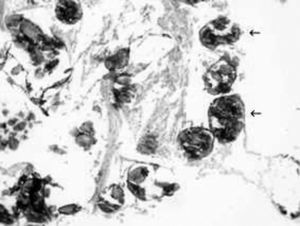

Se le realizó un lavado alveolar (BAL) y una biopsia transbronquial que confirmaron el diagnóstico de microlitiasis pulmonar alveolar, observándose minúsculas calcificaciones intraalveolares, también denominadas microlitos o calcosferitos (fig. 4).

Fig. 4. Hallazgos anátomo-patológicos confirman la presencia de calcificaciones intraalveolares concéntricas (flechas), diagnósticas de microlitiasis pulmonar alveolar.